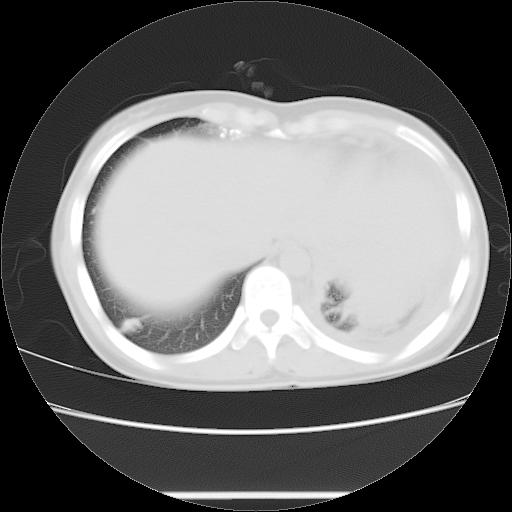

标题: CT21561:外院胸片提示胸腔积液,行CT检查。 [打印本页]

女,29岁,胸部不适,在外院胸片提示胸腔积液,到我院ct检查。

肺窗: